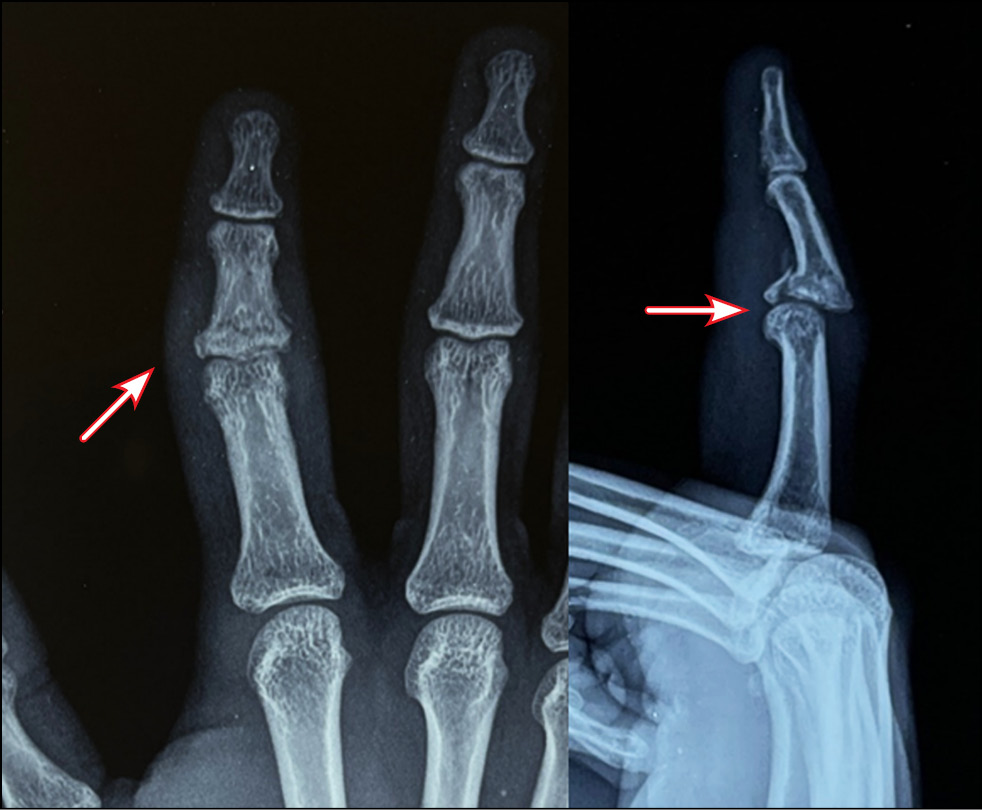

Fig. 14. Appearance and X-ray picture.

Fig. 15. Marking of computed tomography.

In 2021−2022, 23 patients with malunion fractures of the palmar edge of the base of the middle phalanx of the triphalangeal fingers were surgically treated using the hemiarthroplasty method and its modifications. Three patients with damage to the dorsal edge of the base of the middle phalanx accompanied by damage to the central bundle of the common extensor tendon were treated with autograft arthroplasty from the base of the middle phalanx of the second toe. All patients were men; the average age was 51 years (36 to 68 years).

All patients underwent preoperative diagnostics: radiography, computed tomographic study, and clinical evaluation of the range of motion in the joint. According to the radiological and tomographic signs, the fractures of the palmar edge of the base of the middle phalanx with its dorsal subluxation, and in three cases fractures of the dorsal edge of the base of the middle phalanx with palmar subluxation, accompanied by failure of the central bundle of the tendon of the common extensor tendon of the finger, were determined as malunion fractures. According to the Eaton classification, they are categorized as groups IIIa and IIIb. In all cases, the amplitude of movements in PIP joints was sharply limited; flexion was up to 30°. Pain syndrome at the moment of attempted flexion in the joint was assessed by patients ranging from three to four points on VAS.